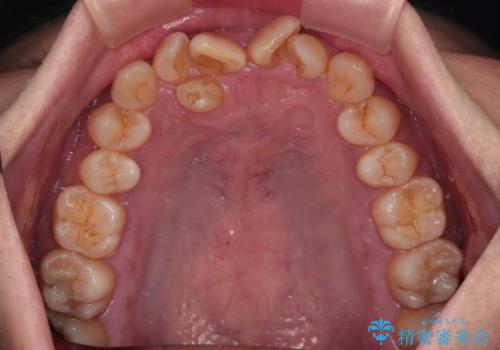

骨格的に上顎骨がやや前方にあり、それが原因で下顎前歯が隠れるほどのディープバイトになっている状態でした。

補助装置を用いて、上顎大臼歯を積極的に後方移動させながら、ディープバイトを改善していくこととしました。